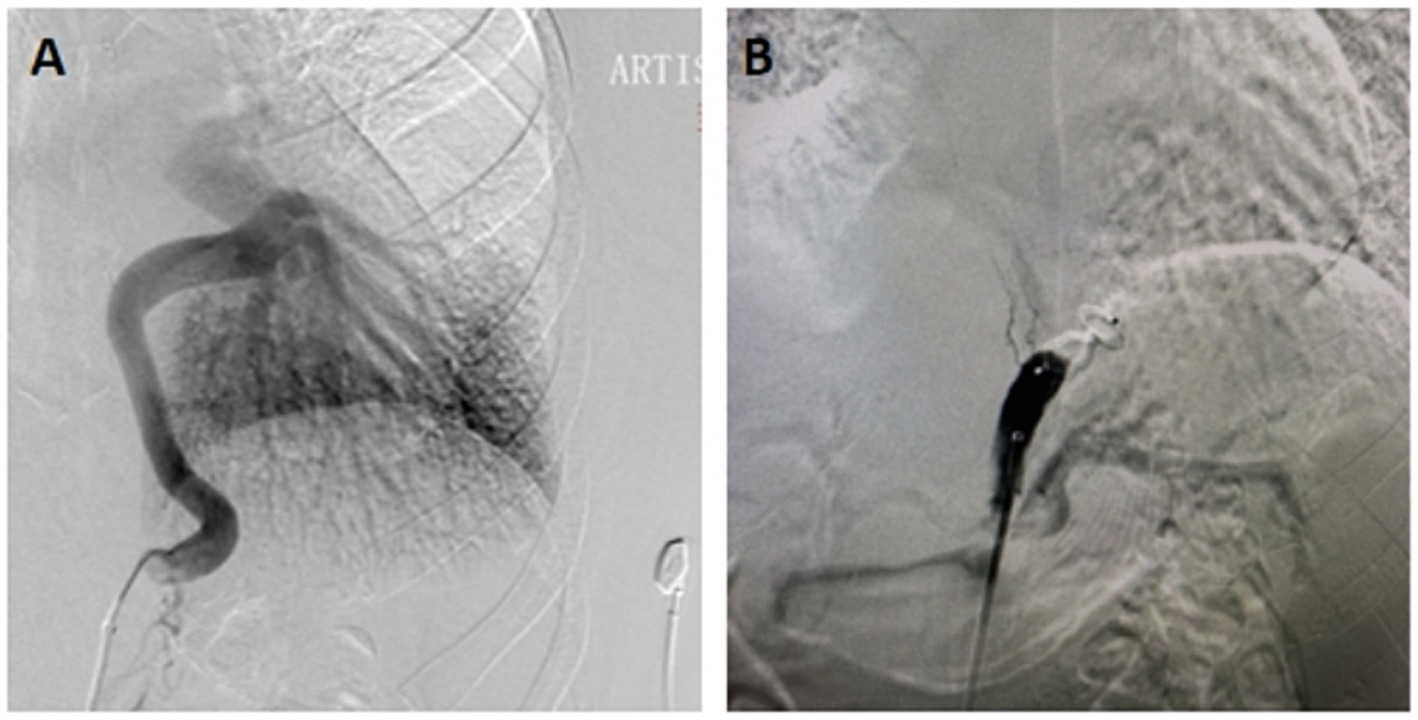

Following the presentation of treatment options, which included surgery, observation, or TAE, the patient opted for the latter due to its minimally invasive nature (Figure 2). Pre-procedural management encompassed a 3-day course of intravenous dexamethasone (5 mg daily) and antibiotics to prevent pulmonary infarction or infected necrosis. Subsequent to embolisation, the patient exhibited resolution of hemoptysis and chest discomfort, with discharge occurring on post-procedural day5.

Figure 2. (A) Angiography showed a large supply arising from the celiac aorta to normal basal segments of the lung. (B) After proximal arterial embolization with AVP, a aortogram showed occlusion of the celiac aorta.